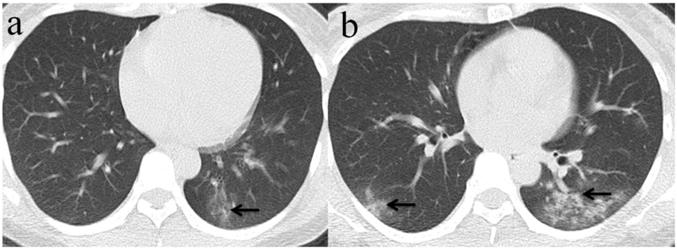

Figure 4

Chest CT imaging findings of COVID-19 pneumonia in a 30-year-old female patient presenting with fever (range:38.1-39℃) for four days. (a) Subpleural GGO was presented in the left lower lobe with initial negative RT-PCR (arrow);(b) 5 days later, there was an enlarged region of GGO and consolidation(arrow) presented in lower lobes of bilateral lung while RT-PCR test turned positive. (arrow).

Among the 32 patients with negative initial RT-PCR and first positive CT, only 25 patients had the second chest CT when RT-PCR test turned positive. GGO was the most frequent CT findings at the first and second chest CT [96.9% (31/32) and 84% (21/25), respectively] (Figure 3), and the right upper lobe (22/32[68.8%]) was the most commonly affected at initial chest CT scan with negative RT-PCR. Consolidation was more frequently observed on the lower lobes, and more frequently detected during the second CT (16/25[64.0%]) with positive RT-PCR than the first CT with initial negative RT-PCR (17/32[53.1%]) (Table 2, Figure 3, 4). More than two affected lung lobes were detected in 65.6% (21/32) patients at the first chest CT, and this ratio went up to 84.0% (21/25) at the second chest CT, while 12/25 (48.0%) patients had all five lobes affected. Bilateral lung involvement was more often than unilateral both at the first (22/32[68.8%]) and second (22/25[88.0%]) chest CT (Table 2). Subpleural distribution characterized the lung involvement in most patients (24/32[75.0%]) at the first chest CT, which presented in 11/25 (44%) patients at the second CT (Figure 5). However, the crazy-paving pattern is not as common at the first (4/32[12.5%]) and second (3/25[12.0%]) chest CT. No patients had cavitation, calcification, or lymphadenopathy.